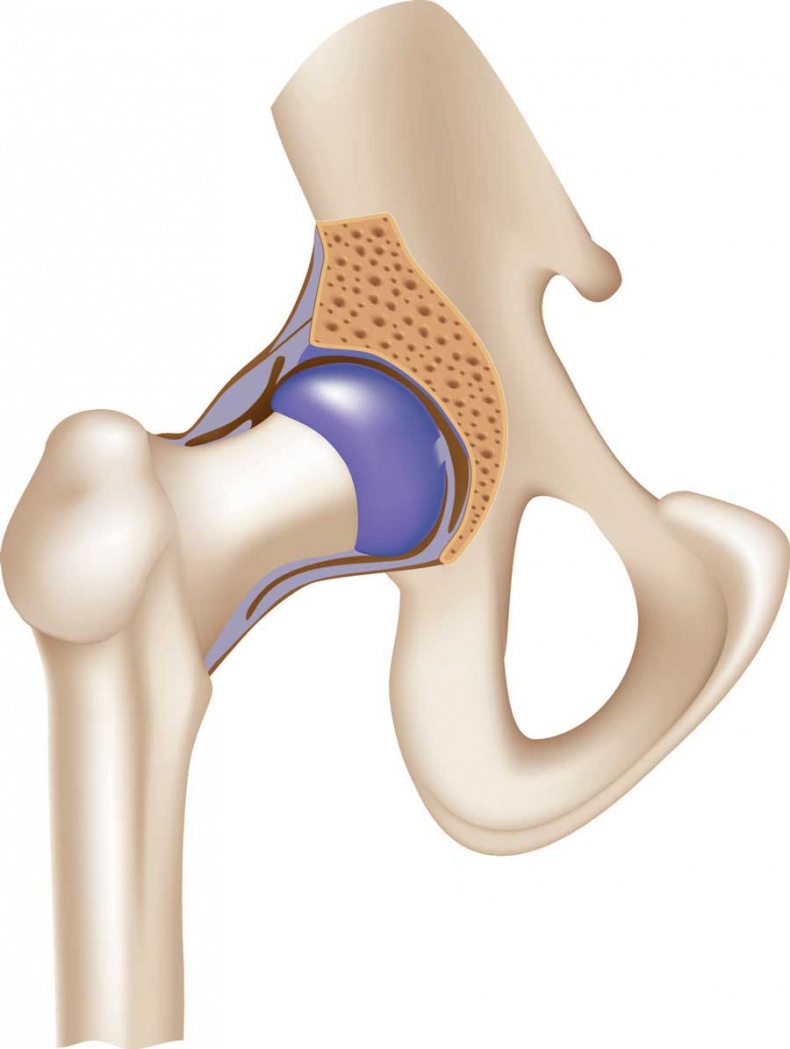

Соединение костей в коленном суставе (вверху – рентген, внизу – модель)

Шаровидный сустав

По форме суставных поверхностей различают плоские, цилиндрические, эллиптические и шаровидные суставы. Наименее подвижны плоские суставы, наиболее – шаровидные.